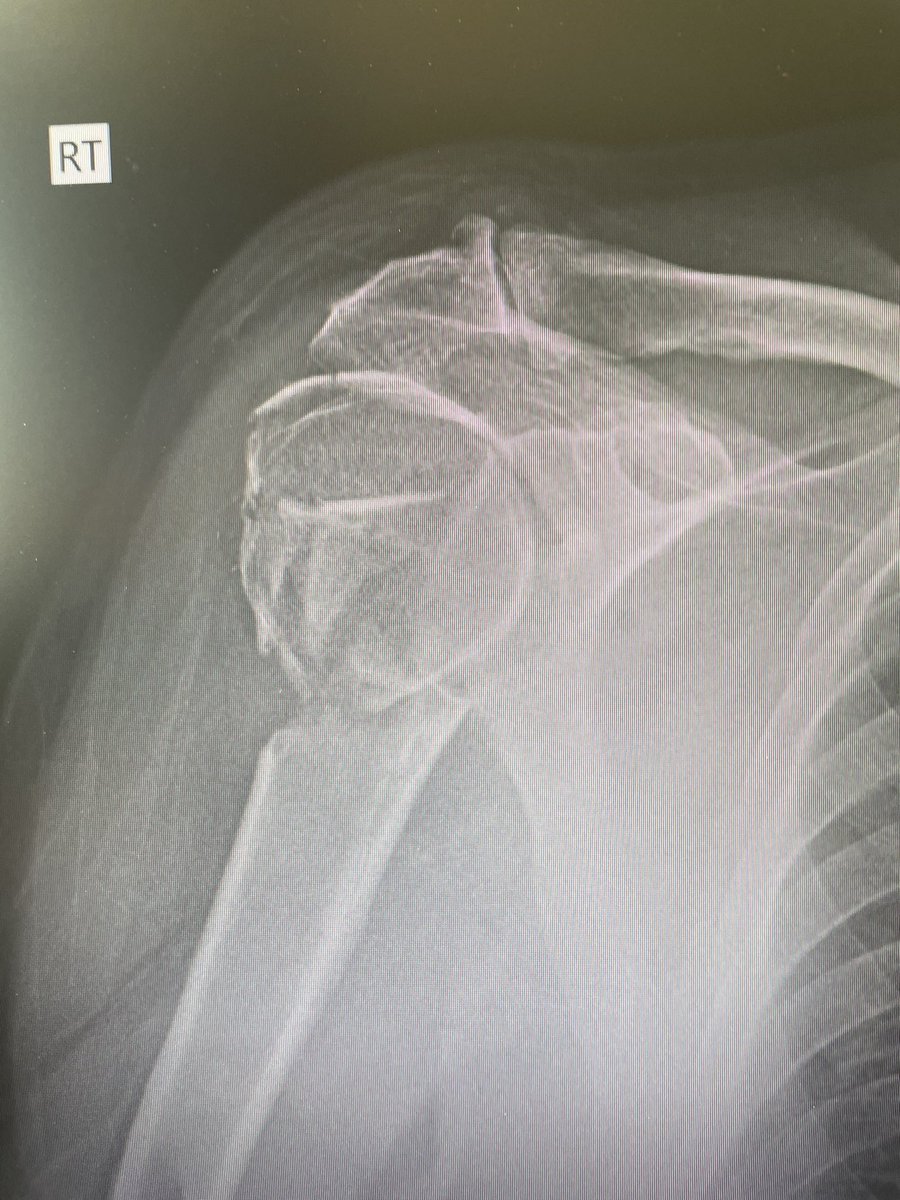

@orthobullets If there is still some cartilage left on the reverse Hill Sachs I’ve had some luck with doing a humeral head osteoplasty. I’ll use allograft chips or cement to backfill the defect after I tamp up articular surface and then try to get everything repaired especially in young pts